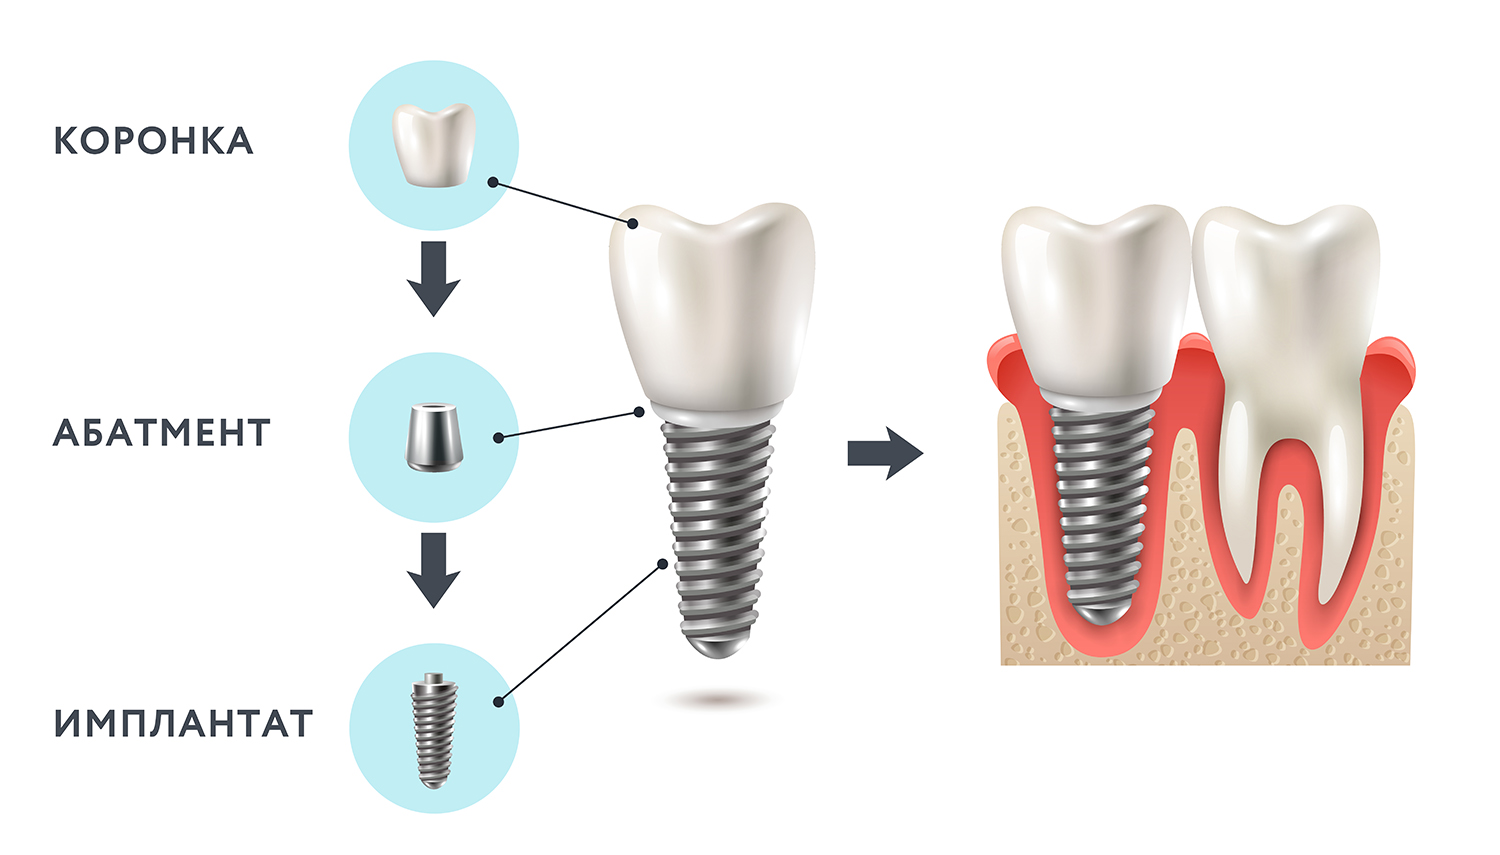

Пошаговое руководство по установке съёмного протеза на импланты